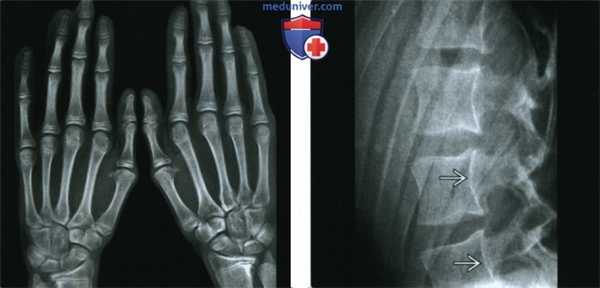

(Слева) Рентгенография кистей в ЗП проекции: определяется арахнодактилия при отсутствии других изменений. Наблюдается аномальный метакарпальный индекс.

(Справа) Рентгенография в боковой проекции, этот же пациент: определяется неровность задней поверхности тел позвонков. Плотность кости нормальная. На уровне позвонков L5-S1 был выявлен двусторонний спондилолизис с IV степенью спондилолистеза (изображение не представлено). Аномалии позвоночника в сочетании с арахнодактилией могут наблюдаться как при синдроме Марфана, так и при синдроме Элерса-Данлоса: в этом случае диагностирован синдром Марфана.